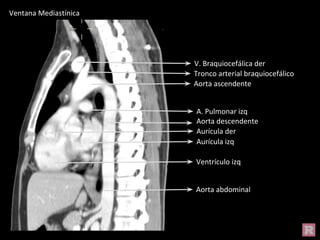

Aorta abdominal

Aorta descendente

Aorta ascendente

V. Braquiocefálica der

Tronco arterial braquiocefálico

Ventrículo izq

Aurícula der

Aurícula izq

A. Pulmonar izq

Ventana Mediastínica